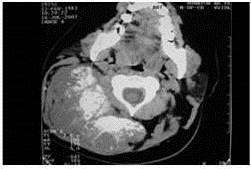

Posteriormente se le realizó tomografía axial computarizada (TAC) de cráneo que concluye: lesión tumoral de densidad mixta con zonas de densidad de partes blandas y calcificaciones de 10 cm x 7 cm en región occipital derecha. En TAC de cuello se evidencia: LOE en partes blandas de región cervical posterior derecha con extensión a región occipital en relación con diagnóstico conocido de la paciente de condrosarcoma (Figura 3).